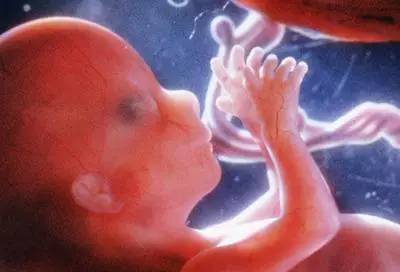

第五个月

胎宝宝身长20-25cm,体重250-300g。皮肤呈暗红色,出现胎脂,此时的宝宝已经长出细茸的头发了。胎宝宝已经开始出现吞咽和排尿了。这个月开始胎儿运动明显增加,10%~30%时间胎动活跃,大部分孕妈已经可以感觉到胎动了。